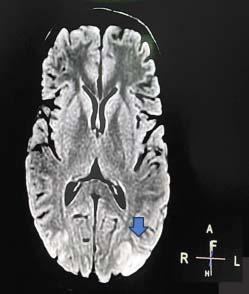

The model (Fig 1) has a classification ability of 80% (Area under ROC curve), with cut off value of 4.5 with 84.1 % sensitivity and 55% specificity. Therefore, a cut off score of 4 was chosen. A total score of <4 suggested Dengue, and >4 suggested Scrub Typhus.

This model was applied to another subset of patients, with 25 patients in each group for both Dengue and Scrub Typhus, and the results were obtained as mentioned in Table 2. The sensitivity was 72% and 48% when applied on patients who were tested positive for Dengue and Scrub Typhus respectively.

1 — ROC curve of age, hemoglobin, TLC, NLR, platelets, total

CRP, albumin and altered sensorium